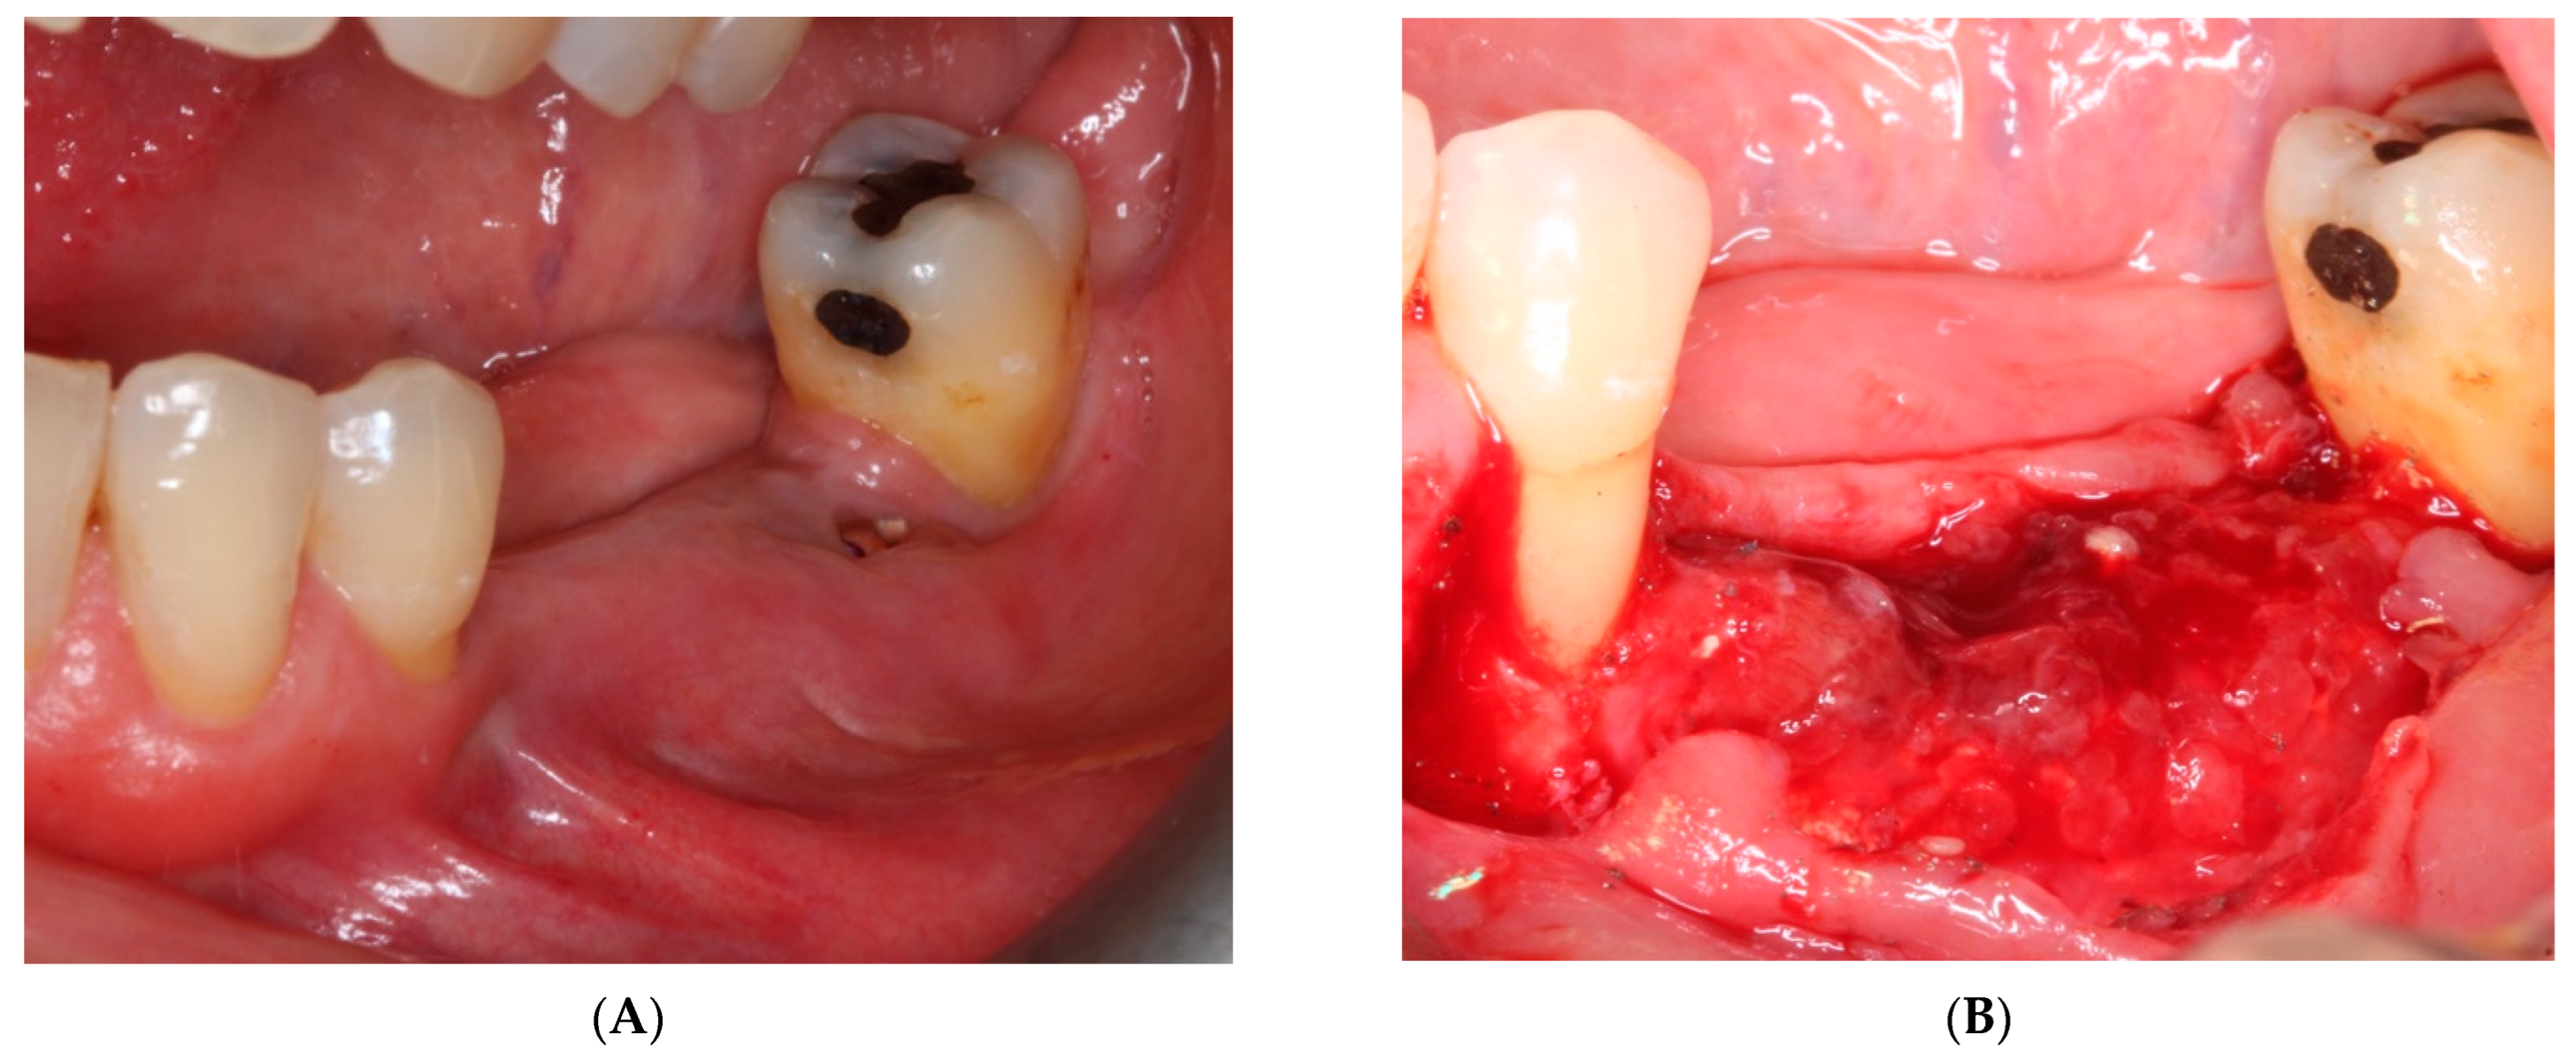

- First surgery: Local anesthesia Articaine 4% with epinephrine (1:100,000) was administered. An intrasulcular incision was made from the mesial of 3.3 to the distal of 3.7, continuing along the anterior border of the external ramus of the mandible. Periosteal incisions were made to mobilize the vestibular flap and the upper fibers of the mylohyoid muscle were disinserted to passivate the lingual flap and thus obtain a tension-free closure (Figure 3). We then checked the position of the mesh and proceeded to collect bone from the ascending branch using the bone scraper (Micross®, Selecdent, Barcelona, Spain) (Figure 4A). Cortical perforations were made to promote bleeding (Figure 4B). We mixed the autologous bone with the xenograft (Tioss®, Sanhigia, Bujaraloz, Spain) in a 70:30 ratio, inserted it into the mesh, and the mesh was placed in the defect.